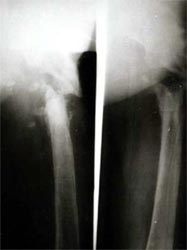

以上图片为三位患者的X线片,显示股骨粗隆下骨折、骨不连,内固定已经失败。

患者股骨粗隆下骨折、骨不连,左图为手术前,显示假关节形成,右图为手术内固定后,关节功能恢复